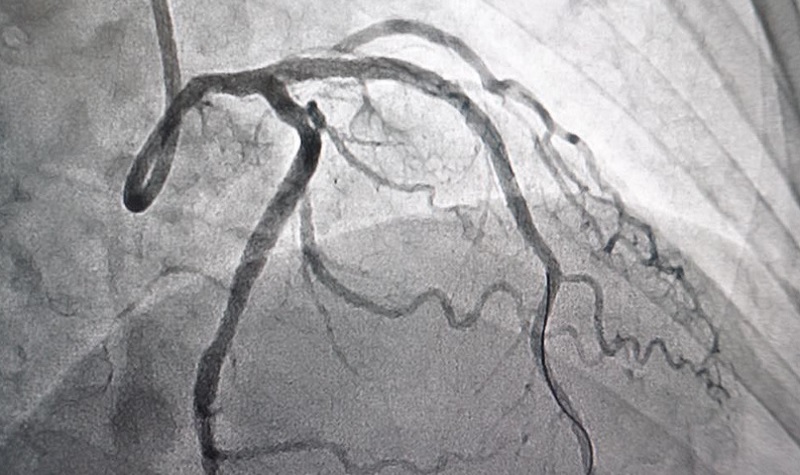

Các phương pháp điều trị rung nhĩ phổ biến hiện nay

Hiện nay, điều trị rung nhĩ không chỉ dừng lại ở việc kiểm soát triệu chứng, mà còn hướng tới mục tiêu lâu dài là phòng ngừa biến chứng nguy hiểm như đột quỵ hay suy tim. Tùy vào tình trạng sức khỏe, mức độ rối loạn nhịp và bệnh lý nền, bác sĩ sẽ lựa chọn phương pháp phù hợp. Trong bài viết dưới...